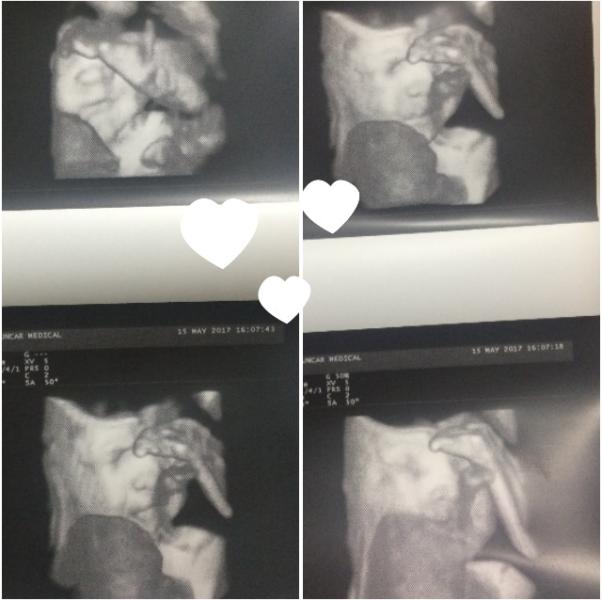

Привееетик девочки)🙋🏻 Как ваши дела? Я сегодня самая счастливая будущая мама на свете! Не терпится поделиться с вами 🙈 Сегодня сходила на ЗД УЗИ и увидела своего сына 👼😍😍😍 Правда он закрывал лицо ручками) Делала все что нужно чтобы он убрал ручки, но он или стеснительный или упрямый как я 😂 Шоколадка 🍫 тоже не помогло( Точно увидела что носик та мооой☺️☺️☺️ А губки конечно папин 😄Счастью нет предела 😇🤰💕 Всем желаю материнского счастье ❤️ Аллага шукир 🙏 (нет кз букв)

@shynybekovnaa, @mama_aldiyarchika, @samara.89, Пасибочки девочки☺️ Делала в "Сункаре" на Маргулана-Момышулы. ЗД УЗИ + фото+ видео = 5500тг стоит. Врач Ким Ольга Юрьевна.Она мне очень понравилось) Все было на высшем уровне 👍 Всем советую🙃😉